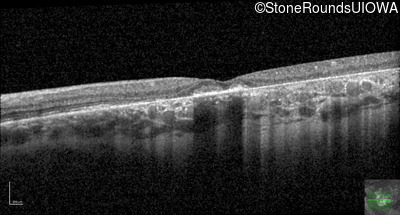

AR Stargardt Disease (IIA)

Age at visit: 61 years

This 61 year old woman first noticed an abnormality in the center of her vision in dim light when she was 8 years old.

Diagnosis & molecular findings

Disease Gene Allele 1 variant(s) Allele 2 variant(s) Inheritance mode

AR Stargardt Disease ABCA4 Pro1380Leu CCG>CTG IVS40+5 G>A AR